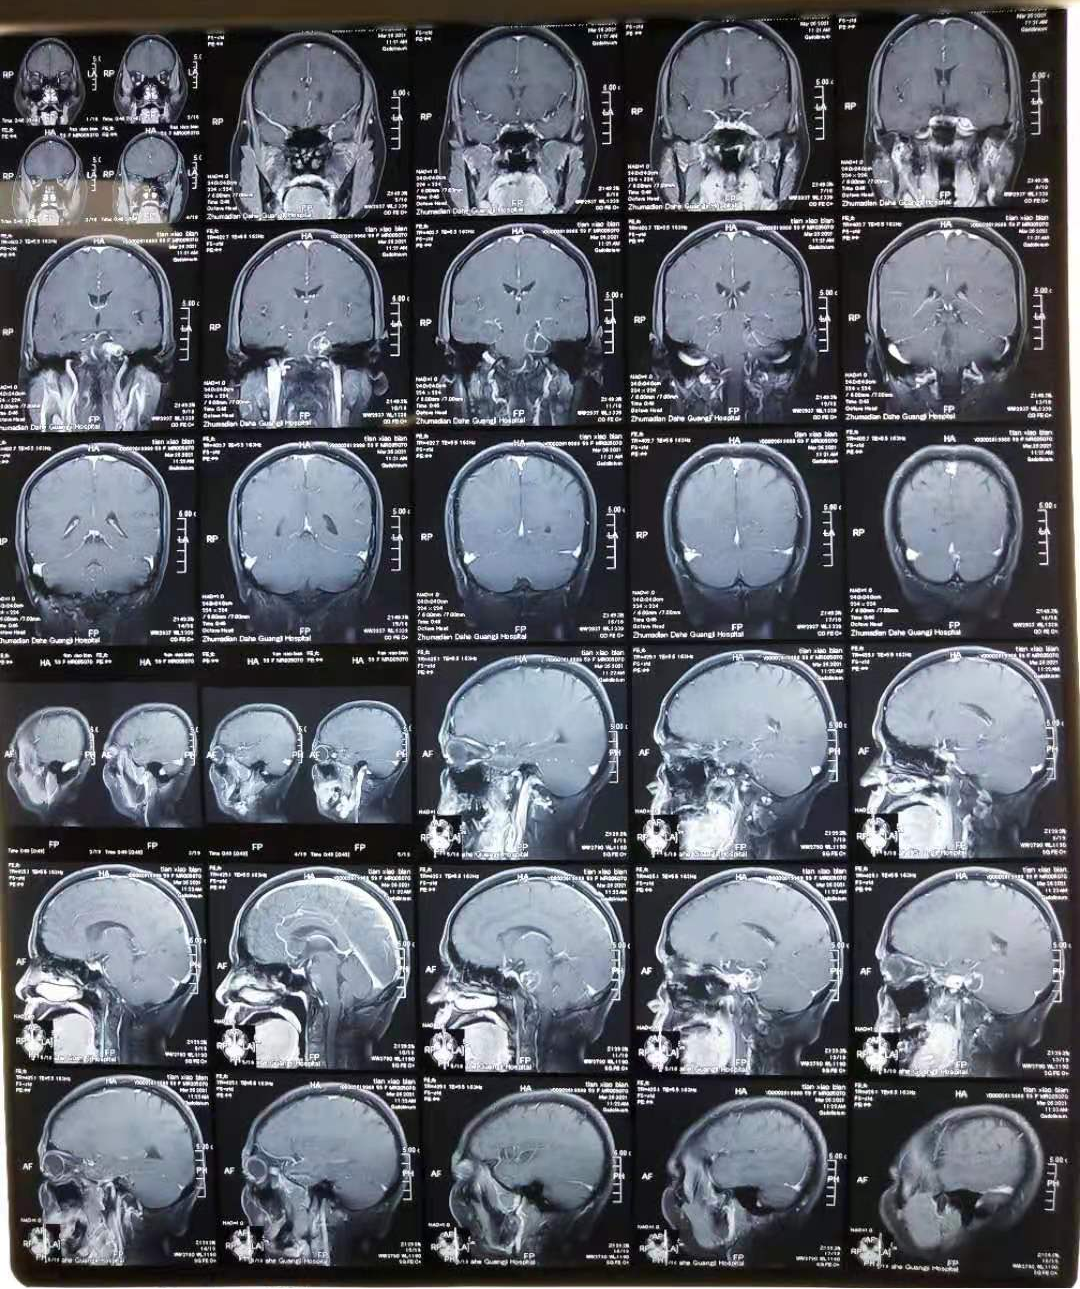

頭部MRI掃描:術(shù)前

影像學(xué)表現(xiàn):橋小腦角多囊性占位,幕上腫瘤侵入海綿竇

影像學(xué)診斷:左側(cè)橋小腦角占位病變。

經(jīng)科室認(rèn)真討論分析,診斷為:“三叉神經(jīng)鞘瘤”,腫瘤跨小腦幕上下,上方已進(jìn)入鞍區(qū)海綿竇內(nèi),幕下占據(jù)橋小腦角,壓迫面聽神經(jīng)。該病例非常少見,病變侵犯中樞神經(jīng)功能區(qū),手術(shù)難度及風(fēng)險極高,經(jīng)術(shù)前充分準(zhǔn)備,2021年4月8日在我院神經(jīng)外科萬傳軍主任、主管醫(yī)生吳凌志主任、宋彥濤醫(yī)生及手術(shù)室同道配合下行顳下經(jīng)巖骨嵴入路腫瘤切除術(shù)。